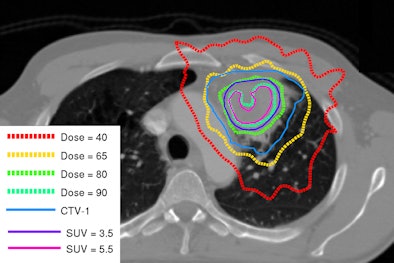

Next, the group decided to investigate dose escalation when delivered "inhomogeneously." NSCLC tumors are heterogeneous in composition, so delivering equal doses across a tumor provides too low a dose to resistant parts, and overkill to more sensitive parts.

"It's more logical to give a heterogeneous dose distribution to a heterogeneous tumor for optimized local control," De Ruysscher said.

| Image shows redistribution of dose according to tumor heterogeneity. Courtesy of Dr. Dirk De Ruysscher. |

An ongoing phase II randomized trial investigating dose redistribution is being conducted with the Netherlands Cancer Institute. Instead of a flat radiation dose across the tumor (all greater than 4 cm for local tumor control), dose is increased in the FDG-positive areas. A radiation dose of 90 Gy in 24 fractions was given to some areas without subjecting normal tissues to an increased dose.

"In the inhomogeneous dose group, nodal areas received 66 Gy in 24 fractions, whilst FDG-positive areas received the highest dose possible, similar to stereotactic body radiation therapy," he said.